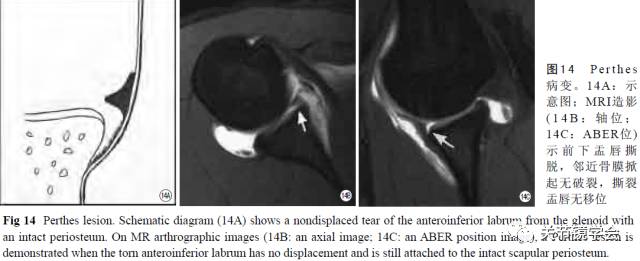

肩关节是人体活动度最大的关节,也是最易脱位的关节,其中,95%为肩关节前脱位。肩关节前脱位的不良后果是容易发展为复发性前方脱位,其原因主要是前下盂唇韧带复合体的损伤。前下盂唇韧带复合体包括下盂肱韧带前束、前下关节囊及前下盂唇,其一端附着于前下骨性关节盂缘,另一端附着于肱骨解剖颈和肱骨干近端。在肩前方脱位时,肱骨头常移位至关节盂的前下方,此瞬间肱骨头后外上方与关节盂前下缘常发生机械性撞击,从而导致关节盂前下缘处软组织或骨损伤,不合并骨折者一般统称为Bankart损伤,合并小骨折块者称为骨性Bankart损伤。少数情况下,前下盂唇韧带复合体损伤可以不发生在关节盂前下缘处,而是发生在肱骨附着部或复合体中部[9]。在MRI上,Bankart损伤主要表现为前下盂唇撕裂或磨损。肩关节MRI常规扫描对前下盂唇撕裂的价值非常有限,因此一般常规进行肩关节MRI造影(图12)。MRI造影轴位T1W为诊断前下盂唇撕裂的可靠手段,敏感性可达80%~90%,特异性可达90%以上;MRI造影ABER位可进一步提高敏感性至95%左右[10-11]。在前下盂唇撕裂的基础上,撕裂可进一步扩展至前上盂唇、上盂唇、甚至后方盂唇。肩关节MRI造影可对Bankart损伤进行更细致的分型,最常见3种类型:①经典Bankart损伤(图13):前下盂唇撕裂并邻近骨膜的断裂,MRI显示前下盂唇四周都被对比剂包绕;②Perthes损伤(图14):前下盂唇撕裂并邻近骨膜的撕脱,但骨膜未断;③ALPSA(anterior labral periosteal sleeve avulsion)损伤(图15):前下盂唇撕裂并邻近骨膜撕脱、伴撕裂盂唇移向关节盂的内、下方[9-11]。